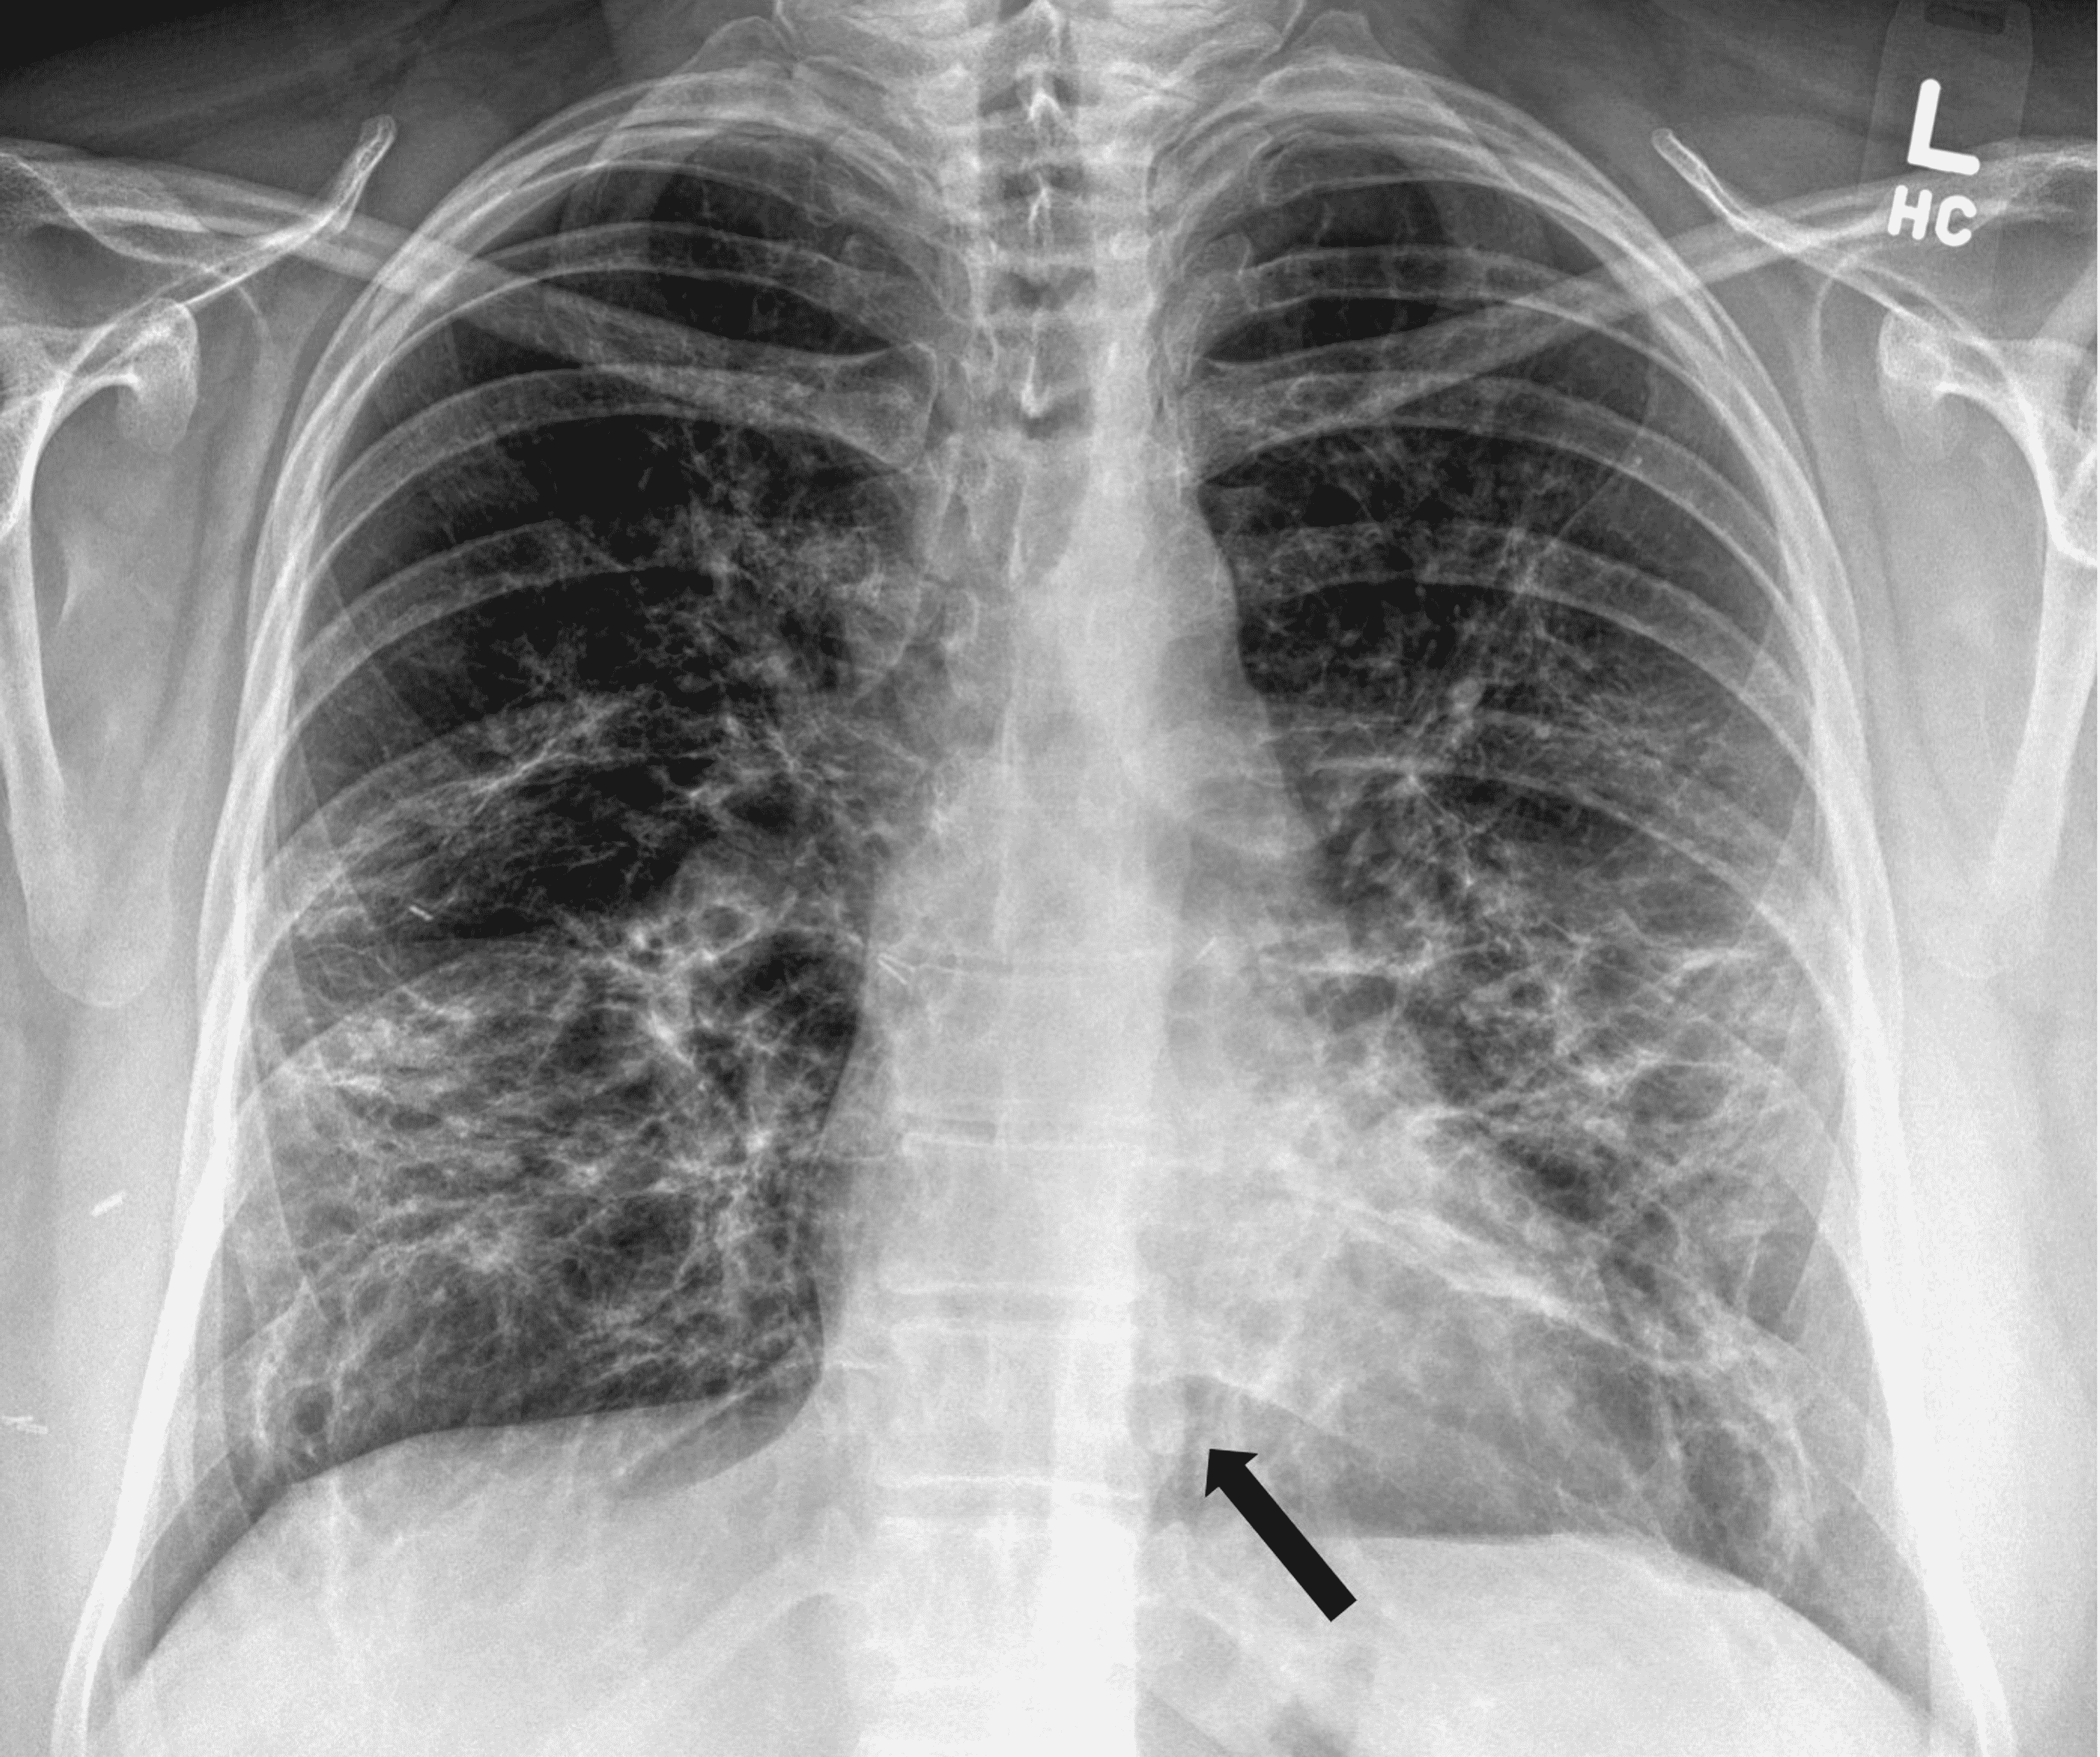

From www.semanticscholar.org

Figure 1 from Diagnosis and treatment of spontaneous pneumomediastinum What Is Spontaneous Pneumomediastinum In the absence of traumatic. Secondary pneumomediastinum is most often caused by. Primary or spontaneous pneumomediastinum refers to a form of the condition with no obvious cause. Spontaneous or primary pneumomediastinum occurs in otherwise healthy individuals with no identifiable cause. Spontaneous pneumomediastinum (spm) is uncommon in children and resolves without specific intervention in most cases. Spontaneous pneumomediastinum (spm) is a. What Is Spontaneous Pneumomediastinum.